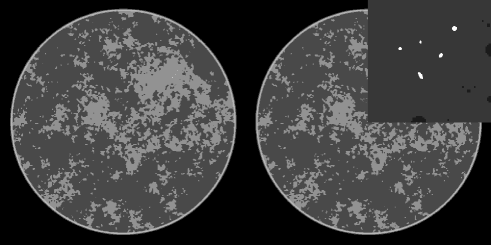

The complete phantom along with a blow-up of a region of interest (ROI) containing the micro-calcifications is shown in Fig. 1. The complexity of background is apparent, and although the phantom is indeed piece-wise constant, the gradient magnitude has 55,000 non-zero values due to the structure complexity. This number is relevant for the CS argument on the accuracy of TV-minimization. While there has been no analysis of CS recovery for CT-based system matrices, one can expect that at least twice as many samples as non-zero elements in the gradient magnitude will be needed for accurate image reconstruction with TV-minimization under noiseless conditions.

For this initial survey of a breast CT simulation, we show two main sets of results. The first set of images are reconstructed from noiseless data for different numbers of views. The idea is to see how well TV-minimization performs in recovering the complex breast phantom under ideal conditions. The second set of images includes noise at a fixed exposure, and as described in Sec. II-B, the noise-level per projection increases with the the number of projections.

IV-A image reconstruction from noiseless data

In Fig. 2, we show images reconstructed from 64 to 512 projections for both TV-minimization and filtered back-projection (FBP). For TV-minimization in this study we set , which corresponds to a very tight data constraint. As noted above the sparsity of the gradient magnitude is on the order of 50,000. Accordingly, from CS-based arguments, one could only expect to start to achieve accurate reconstruction when the number of measured line integrals exceeds 100,000, which in this case means 100 projections. An important part of CS theory deals with computing the factor between the sparsity level and necessary number of measurements for accurate recovery. This factor is unknown for TV-minimization applied to the X-ray transform, but we can see from the reconstructions that the accuracy is greatly improved in going from 128 views to 256 views. There is still a perceptible improvement in the image recovery in going to 512 views, which still represents an under-determined system despite the fact that 512 views is normally not thought of as a sparse-view data set. Again, it is the complexity of the phantom which is responsible for this behavior. The accompanying FBP results give an indication on the ill-posedness of reconstruction from the various configurations with different numbers of projections.

The results for the micro-calcification ROI are interesting in that this particular feature of the image is recovered for all data sets down to the 64-projection data set. This is not too surprising because the micro-calcifications are certainly sparse in the gradient magnitude. But this result emphasizes that the success of an image reconstruction algorithm depends also on the imaging task and the subject.

For the larger goal of determining the optimal number of views, it is clear that ”structure noise” – artifacts due to the complex object function– can play a significant role for this breast phantom.